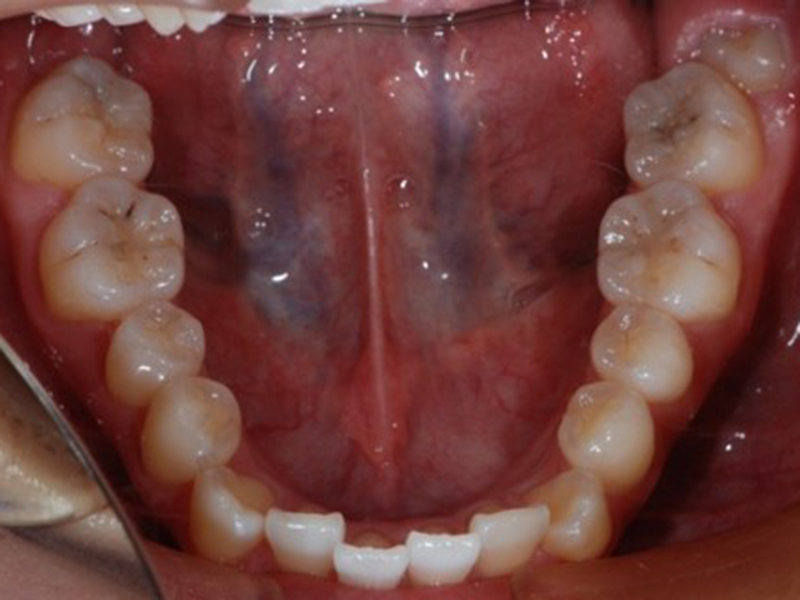

before

経過